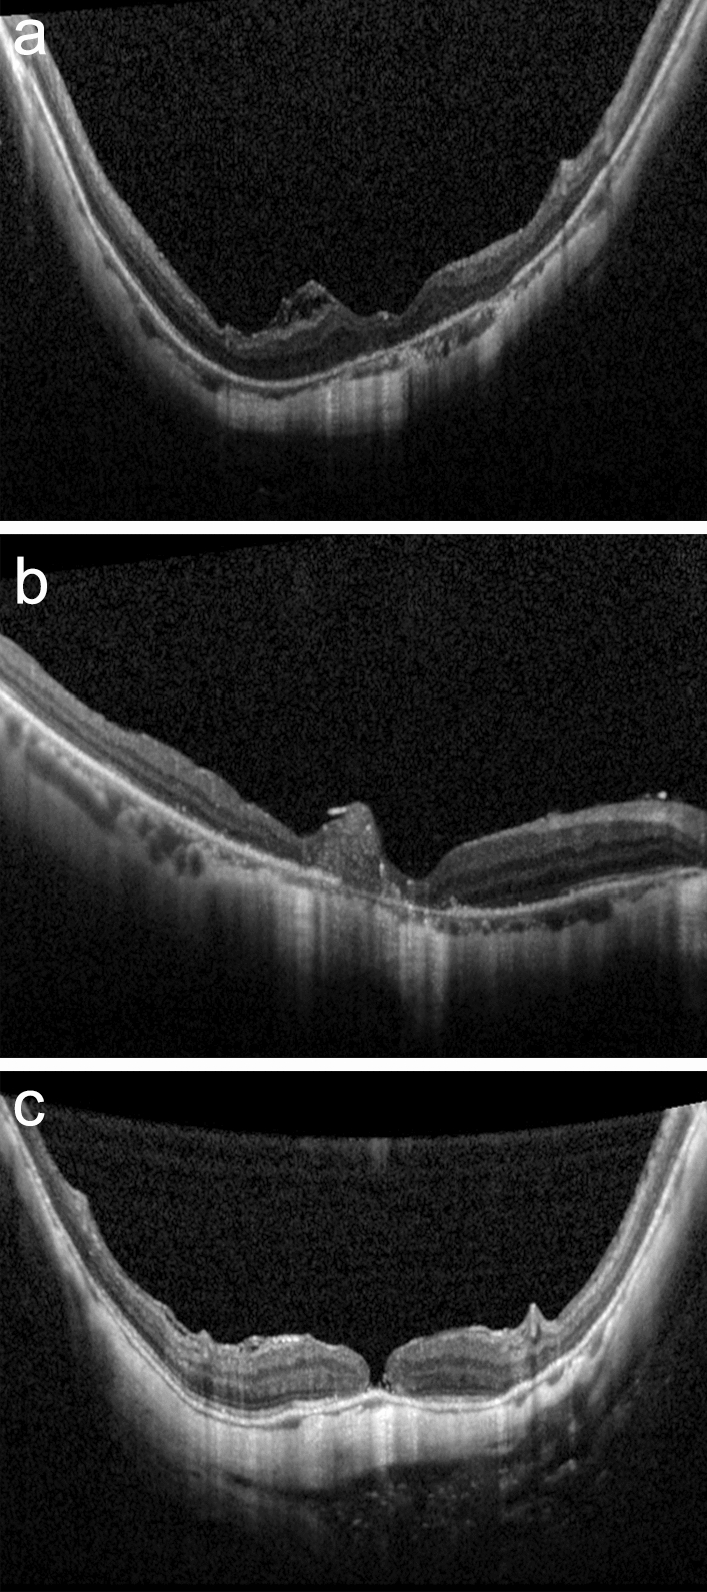

Background: To investigate the anatomical and functional outcomes of macular hole-associated retinal detachment (MHRD) after vitrectomy using the inverted internal limiting membrane (ILM) flap technique with autologous blood clot (ABC).

Methods: This retrospective observational study included 80 eyes with MHRD that underwent vitrectomy with ILM flap without (46 eyes) or with ABC (34 eyes). Fundus photography and optical coherence tomography were evaluated. The pre- and postoperative best-corrected visual acuities (BCVAs) and BCVA improvement were compared between the two groups.

Results: The MH closure rates after initial surgery were similar in the ILM flap group and ILM flap with ABC group [40 (87%) vs. 29 (85%) eyes, respectively]. The proportion of eyes with hyperreflective bridging tissue (HBT) was lower in the ILM flap group than ILM flap with ABC group [13 (32%) vs. 16 (55%) eyes, P = 0.060]. The postoperative improvement in BCVA was significantly better in the ILM flap group (P = 0.027). Multiple linear regression analysis revealed that preoperative BCVA was positively associated with postoperative improvement in BCVA (β = 0.638, P = 0.000), while the ILM flap with ABC technique was negatively associated with postoperative improvement in BCVA (β =  - 0.299, P = 0.039, adjusted r2 = 0.415).

Conclusions: The inverted ILM flap technique alone resulted in better foveal configurations and visual outcomes than the ILM flap technique combined with ABC in patients with MHRD.

Abstract Image